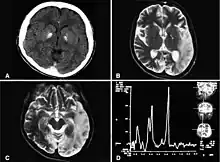

| Basal ganglia calcification, cerebellar atrophy, increased lactate; a CT image of a person diagnosed with MELAS | |

MRI: Multifocal infarct-like cortical areas in different stages of ischemic evolution, areas that do not conform to any known vascular territory. Initial lesions often occur in the occipital or parietal lobes with eventual involvement of the cerebellum, cerebral cortex, basal ganglia, and thalamus.

Lactate levels are often elevated in serum and cerebrospinal fluid. MR spectroscopy may show an elevated lactate peak in affected and even unaffected brain areas. Muscle biopsy shows ragged red fibers. However, genetic evaluation should be done first, which eliminates the need for muscle biopsy in most cases. Diagnosis may be molecular or clinical: